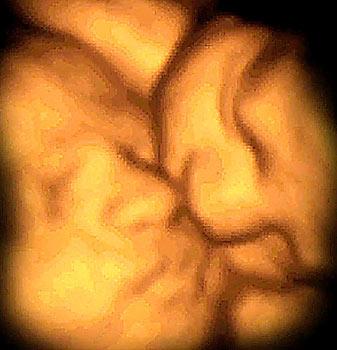

子宫中20-30周大的双胞胎胎

任何一个家庭应该都不会允许一张双胞胎互相依偎,彼此亲吻的照片被外人看到。然而,使用最新的4D超声波扫描技术对子宫进行拍摄得到的照片,可以看到双胞胎在子宫中的亲昵动作可能更加夸张和出格。

传统超声波扫描技术通过使用很高频率的超声波进行扫描,从而对身体内进行成像,4D超声波扫描技术就是在此基础上发展起来的。传统超声波扫描的超声波是由放置在妈妈腹部的传感器或探测器发射出来的,通过移动传感器或探测器,就可以观察到子宫内的图像。这些超声波被胎儿反射回来后,就可以在屏幕上形成一幅胎儿照片。新型4D超声波扫描技术与传统超声波扫描一样,也使用相同频率的超声波,不同之处在于,4D超声波扫描采取多个角度进行扫描的方法,从而可以产生一部胎儿运动的实时录像,同时还允许科学家从四个角度对胎儿进行拍照。

这项新技术使科学家摆脱了以前胎儿静止图象的限制,允许记录胎儿成长的历程,同时,也能观察到双胞胎或三胞胎如何在子宫内争夺地盘或是彼此相拥,互相亲昵。根据4D成像,科学家可以看到令人惊讶的多胞胎电脑成像,还能制作出与实物大小一样的模型。